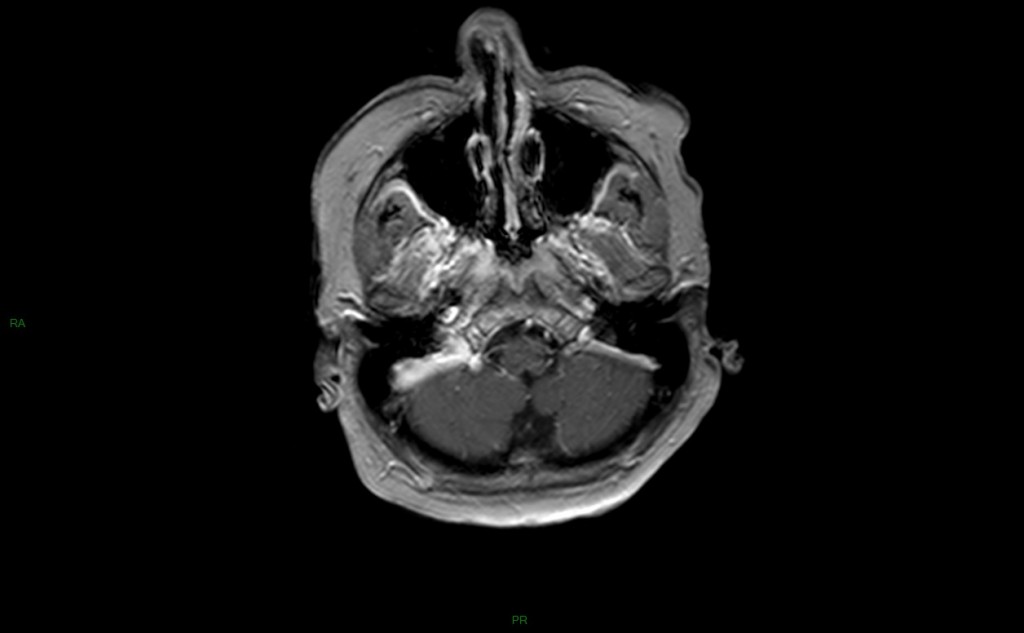

Cryptococcose

• Cryptococcus neoformans

• Inhalation de forme larvaire

• Dissémination hématogène au SNC

• Associé au VIH, hémopathies et maladies de système

• Céphalées, fièvre, troubles de conscience, épilepsie

• IRM

• Aspect de méningite non spécifique

• Dilatation kystique des espaces de Virchov-Robin

• Atteinte des régions putamino-caudées

• Symétrique

• Lésions kystiques

• HypoT1

• HyperT2

• Pas de PDC